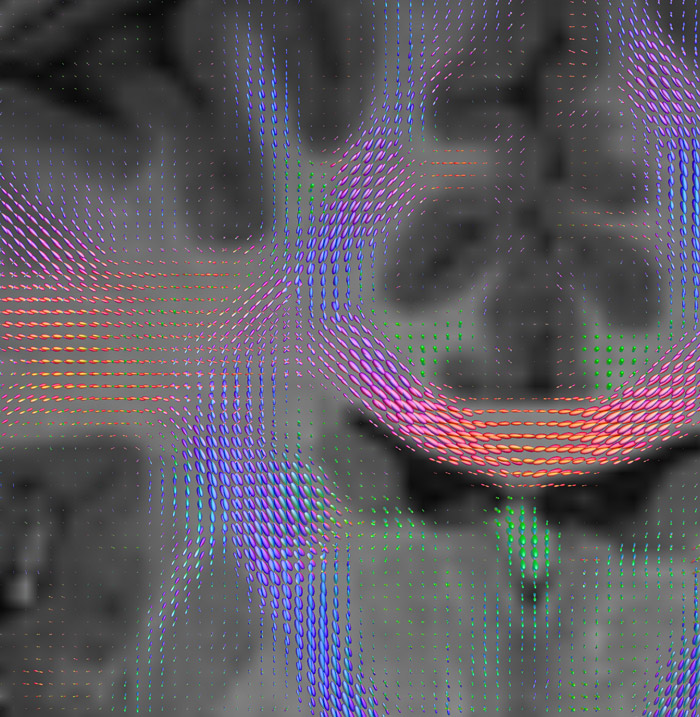

Fiber orientation density

CSD of multishell DWI results in the white matter FOD at each voxel. Unlike the conventional diffusion tensor model, this approach enables accurate modeling of multiple fiber populations within a single voxel.

Crossings of the corpus callosum, corticospinal tracts, and the superior longitudinal fasciculus are shown.

Crossing fibers of the corpus callosum bordered by the superior longitudinal fasciculus as well as within in the pons.